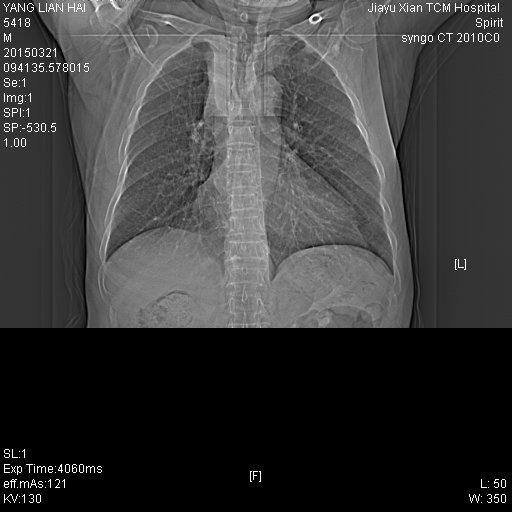

CT50105:患者,男,78岁,因咳嗽一周余来诊

右上纵隔可见带状软组织密度影,与大血管分界不清,右上叶支气管受压, 考虑纵隔型肺癌可能性大。

右上肺中央型肺癌

右上肺中央型肺癌并肺不张

右肺上叶中央型肺癌并阻塞性不张,建议支气管镜检查。

纵隔病变?建议增强。

右上叶中央型肺癌并不张